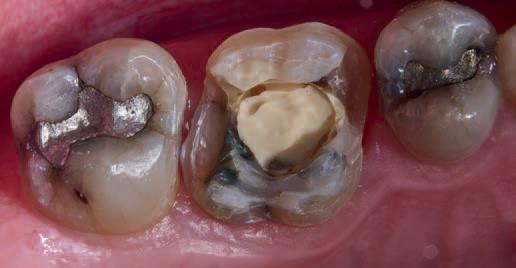

No teeth were tender to percussion. Tooth 26 reacted strongly to cold testing while the other teeth reacted normally. Tooth 26 tested positive to biting on damp gauze but the sensation did not linger. Both tooth 27 and 25 were negative to the bite test. The composite resin restoration in tooth 26 was removed under rubber dam and crack lines could be seen under the restoration (Fig. 1), with the most obvious running from the lingual to the centre of the tooth, and another from the mesiobuccal to the centre. A number of other minor cracks were visible, including one that ran under the buccal cusps (Fig. 1).

Fig. 1

a core material for indirect restoration